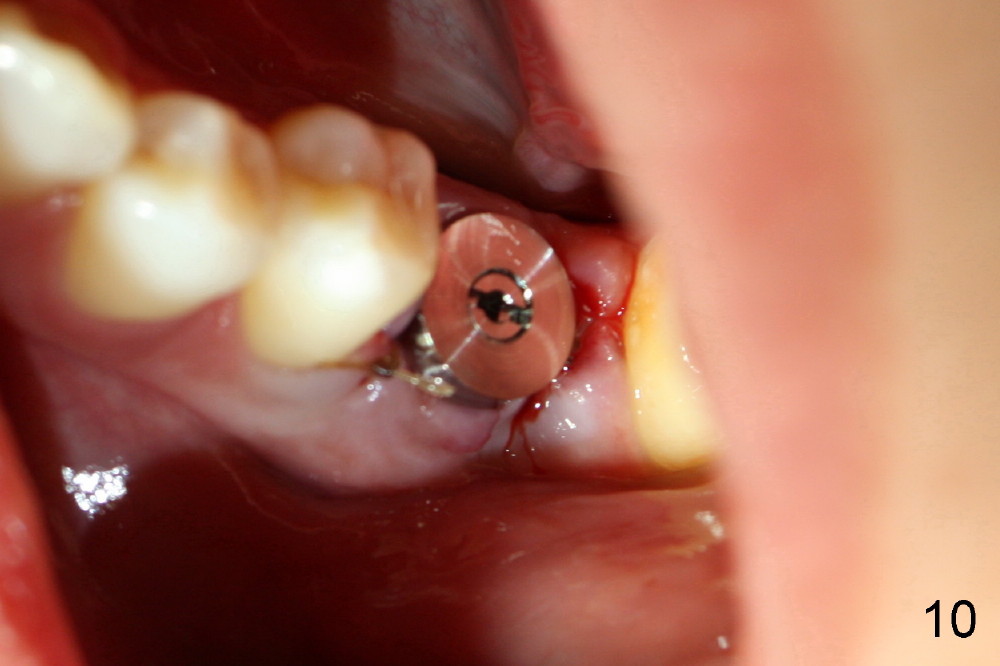

When 7x17 mm tap is placed, it drops mainly into the mesial socket (Fig.8). The septum appears to have been pushed to the distal one (<). When the 7x17 mm implant is placed with primary stability, the top portion is in the middle of the edentulous space (Fig.9). Sutures are placed mesial and distal to close the socket (Fig.10). The wound heals normally 3 months postop (Fig.11: ^). There is no bone resorption; the bone density on the top of the distal socket increases (Fig.12: D). The crown is fabricated 1 month later.